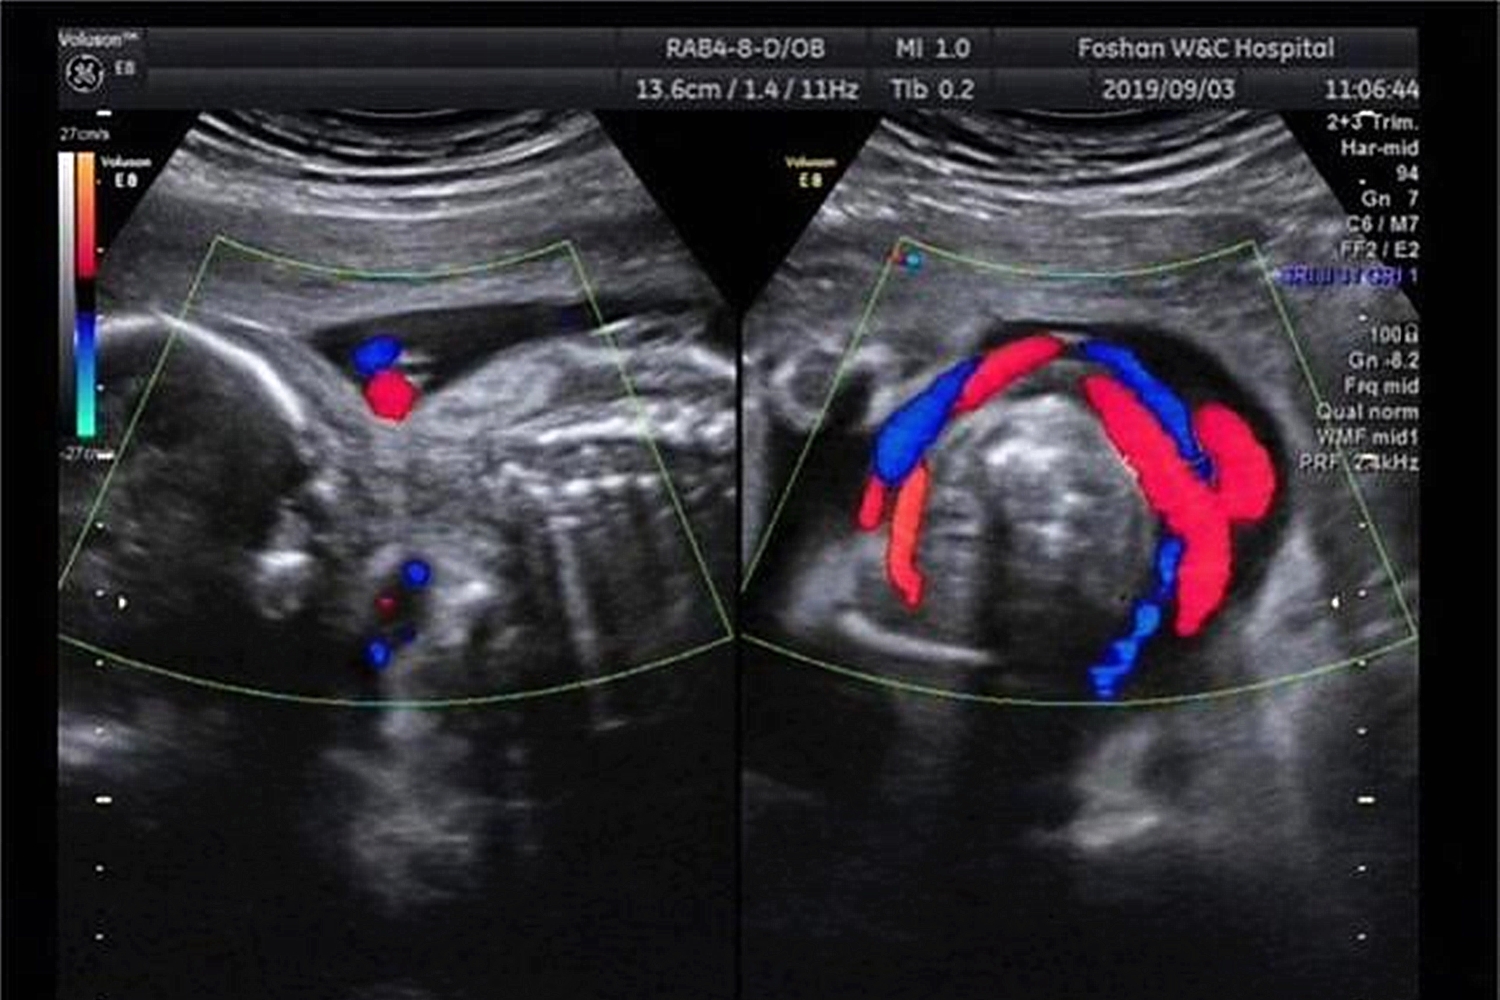

但在刘静妊娠第24周产检时,医生通过四维彩超检查,发现胎儿现况,当时胎儿的情况是脐带绕颈一周,且通过四维彩超和黑白彩超发现在胎儿的旁边有“脐带有打结”的现象。

“脐带有打结”对于胎儿来说是非常危险的事情。一旦胎儿动得厉害,脐带的结被打死了,只需短短几分钟,胎儿就会面临窒息的危境。

脐带是胎儿的营养的供给通道,脐带打结后营养将无法再输送到胎儿体内,最终胎儿将会终止发育胎死腹中。

脐带打结分为真结和假结,其实在生活中真结并不多见。

真结产生的原因是由于宫内的脐带生长过长,在内部形成一个环套而胎儿在生活在那个发育时,穿过了环套,打成了一个结扣。

但一般在未拉扯的情况下,脐带还是宽松的环绕在宫腔内,对胎儿是没有影响的,若结扣有逐渐打死的趋势使血液循环受阻,影响胎儿发育严重时会发生胎儿死亡的危险。

假结就是脐带在宫腔内呈现堆叠现象,在彩超中无法确认内部是否有结,一般假结是没有危险的,很少会有血管破裂出现。